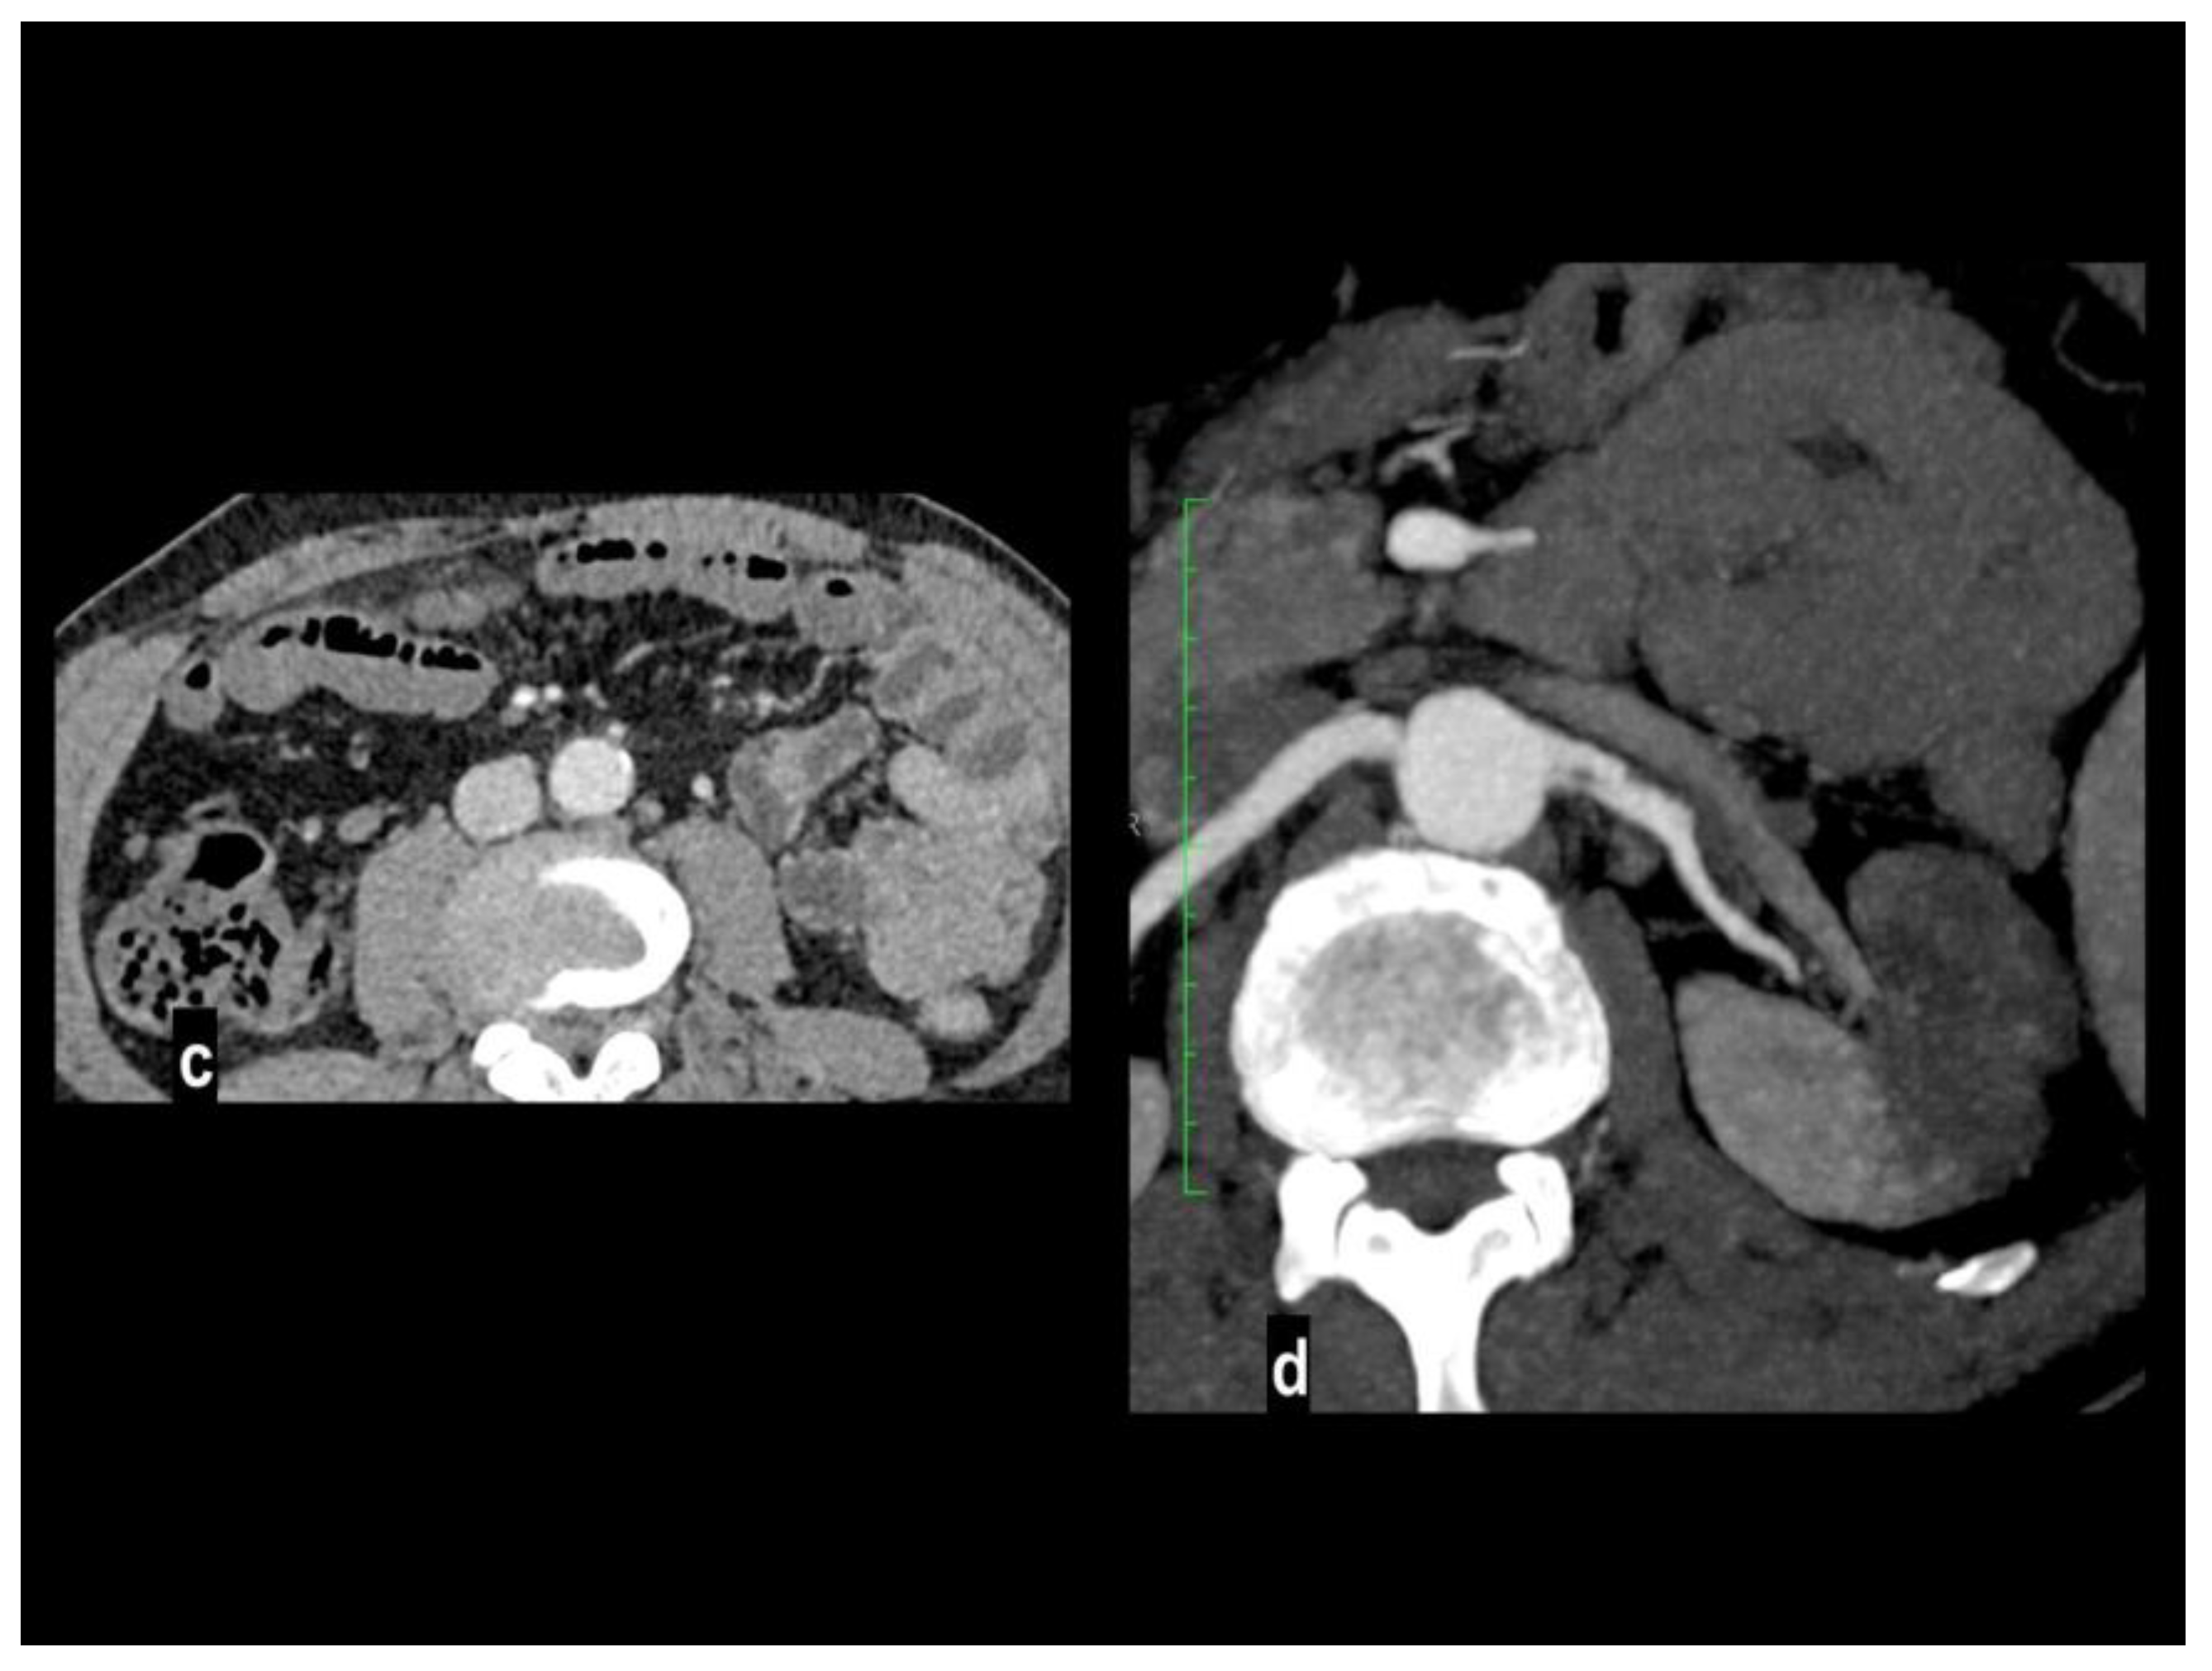

Preprints 106216 g002

Figure 3. Acute abdominal pain in a 52-year-old with atrial fibrillation. Oblique sagittal and coronal MIP arterial images showed embolic occlusion of the middle SMA, with subtle peripheral segmentary enhancement of distal lumen by a collateral vessel (figure 3a-b). Hypoenhancing ileal and right colon walls were well appreciated in comparison to jejunal loops on left abdominal side (figure 3c). A left renal infarct is also present (figure 3d). Patient underwent a right colectomy.